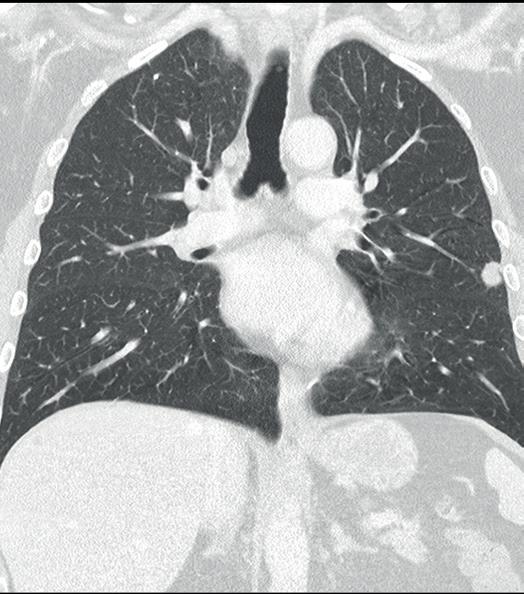

Amanda Smolock (Medical College of Wisconsin, Milwaukee, USA) discusses how her practice operates, using microwave ablation nearly exclusively for primary and metastatic liver tumours targetable under ultrasound (US) and/or computed tomography (CT) guidance.

Patients are typically discussed at a multidisciplinary liver tumour conference and referred to the interventional radiology (IR) clinic for evaluation. At consultation, a full history and physical exam is completed along with updated laboratory studies, including complete blood count, liver function studies, and coagulation tests. Patients with good performance status and preserved liver function are considered appropriate for percutaneous liver ablation. Contrastenhanced (CE) CT images or magnetic resonance images (MRI) are obtained within one month of evaluation and procedure. US assessment is performed at the clinic visit to ensure sonographic visibility and percutaneous approach for ablation. The approach is communicated with the procedure team and helps to streamline preparation on the procedure day.

Procedures are scheduled for general anaesthesia in the interventional CT suite and proper patient positioning for the procedure is a team effort: a posteriorly located tumour may require oblique positioning of the patient, and safe positioning of arms overhead improves CT image quality.

Non-contrast and multiphasic CE-CT are typically obtained prior to probe placement. This helps to review anatomy pre-procedure, confirm tumour location and size, and optimise the percutaneous approach. When possible, probes are placed under direct US guidance. Few cases have tumours visible only on CT or only after lipiodol staining with transarterial chemoembolization (TACE). In these cases, CT navigation software is used to optimise probe placement, which is often best in double oblique approaches to maximise both safety and efficacious tumour treatment. Respiratory manoeuvres in concert with the anaesthesiology team are utilised as

needed to accurately and precisely target tumours with ablation probes. A non-contrast CT is obtained to confirm and document probe position. Hydrodissection and/or biopsy, if being performed, are done after securing ablation probe position(s). CT and US are complementary imaging to confirm appropriate tumour targeting and predict ablation zone coverage. Activated probes and ablation zone formation are monitored in real time with US and intermittent CT. This allows for confirmation of ablation zone formation and coverage.

Another CE-CT is obtained at the conclusion of the ablation. Total contrast volume is split between pre- and post-ablation CE-CT, not to exceed 150–200ml of iodinated contrast agent. Post-ablation CE-CT assesses ablation zone coverage of the tumour with adequate margins and also evaluates for any complications. If margins are inadequate, additional ablation can be performed at this time.